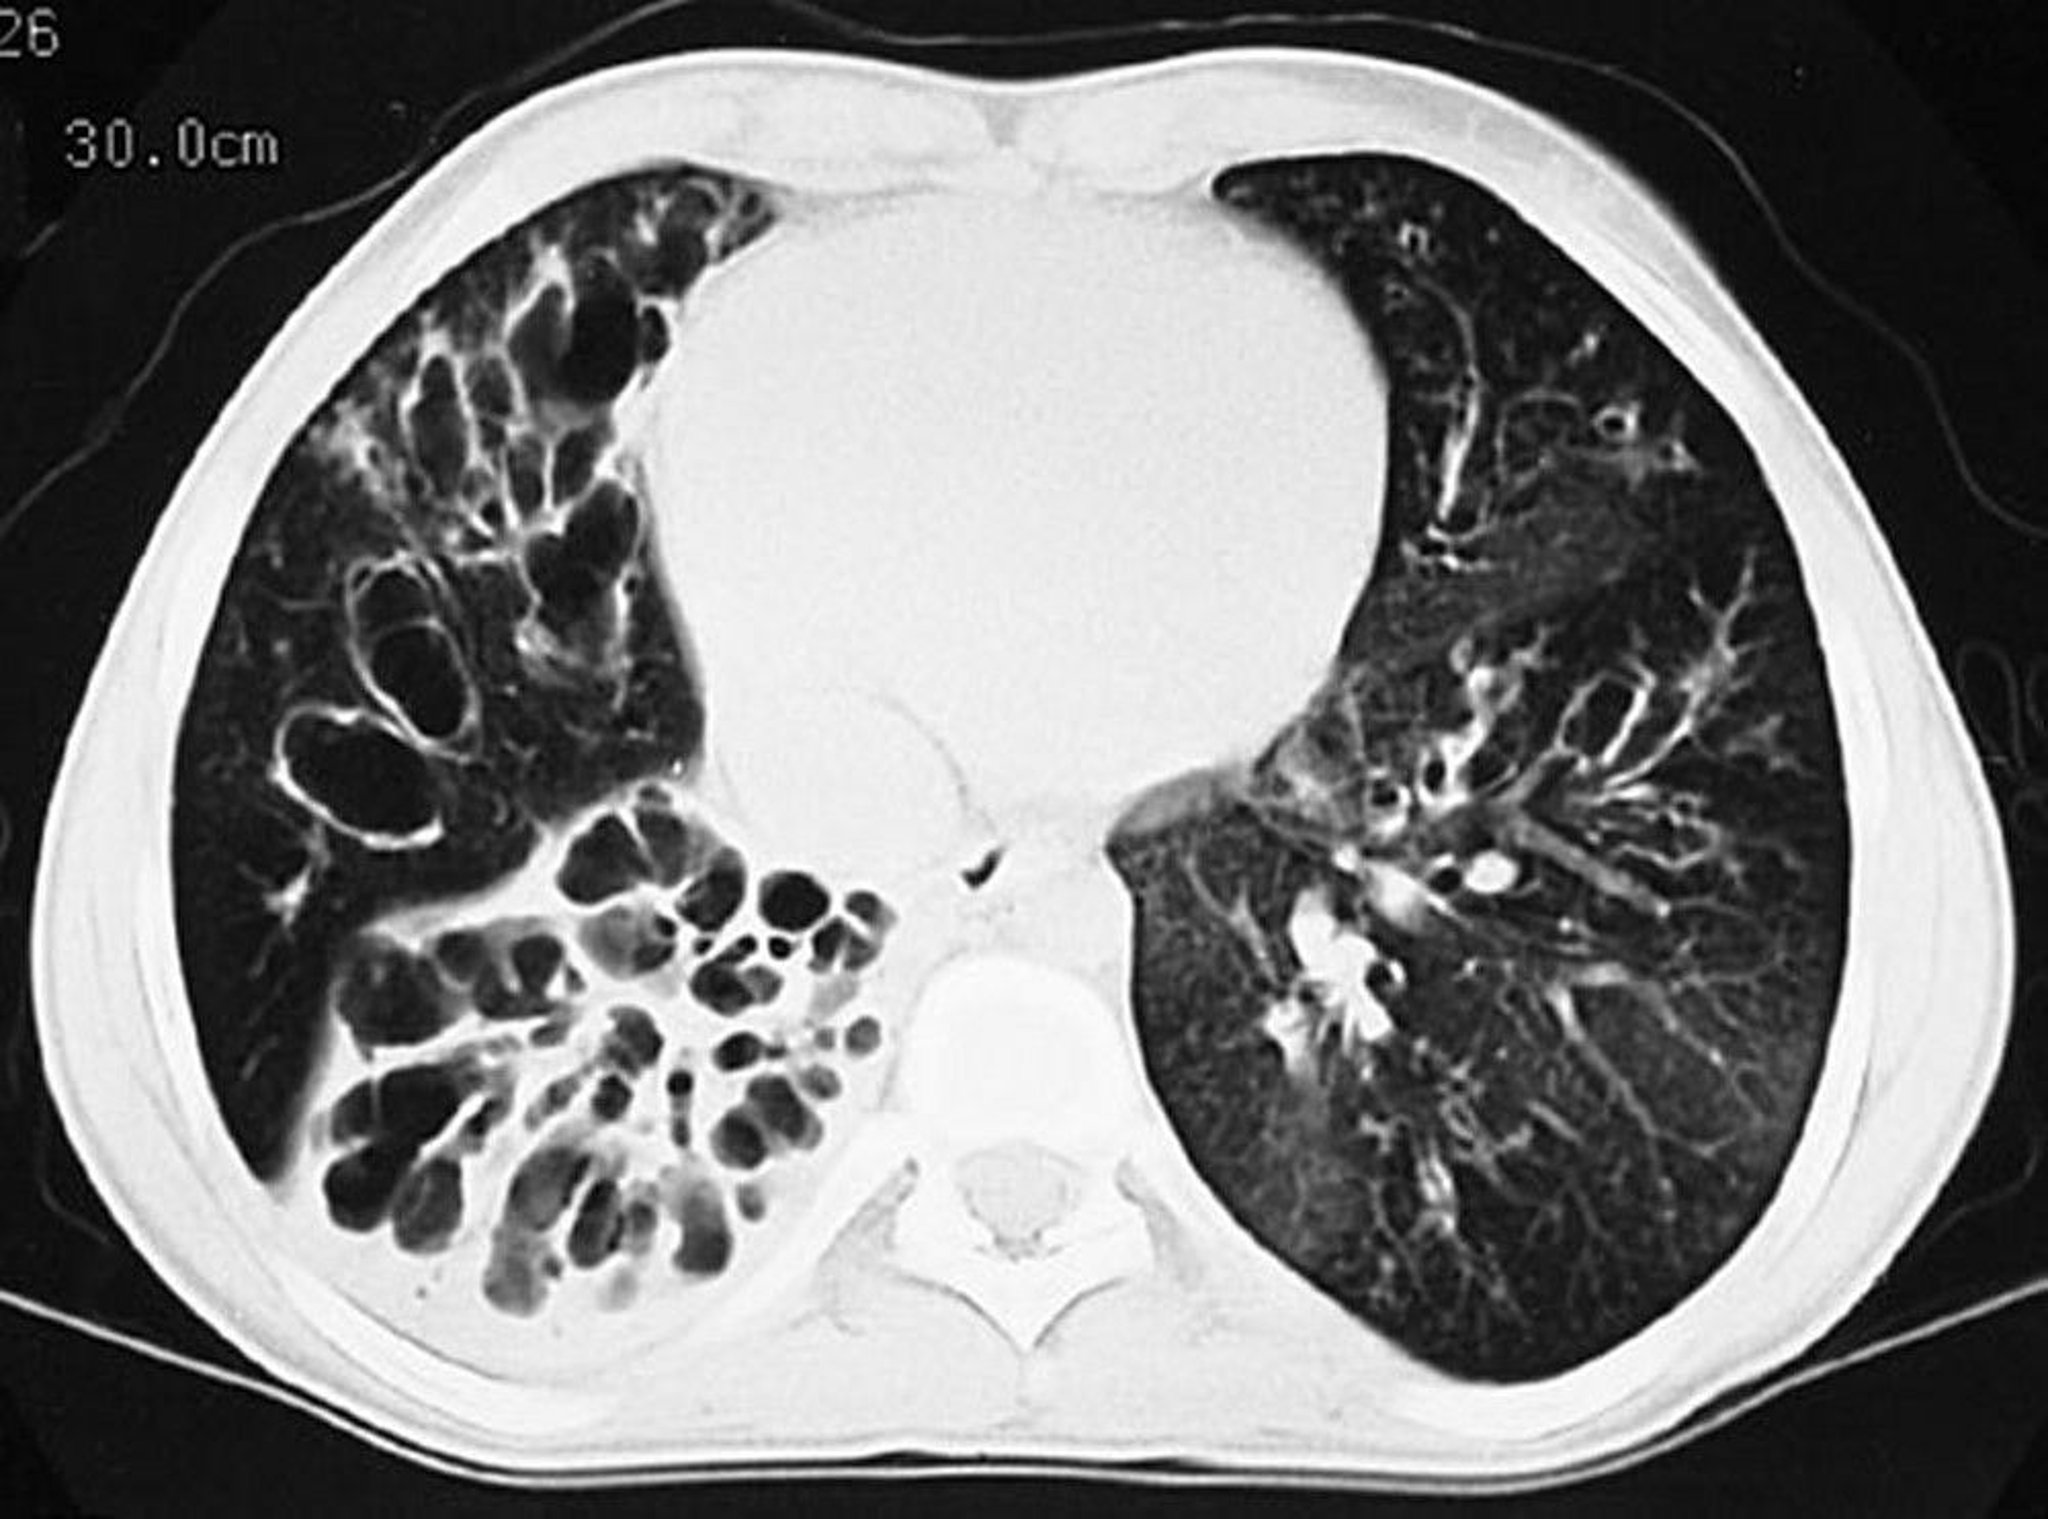

Cystic Fibrosis (CT Scan)

This CT scan shows greatly dilated bronchi throughout the lungs. Findings are typical for CF but not specific.